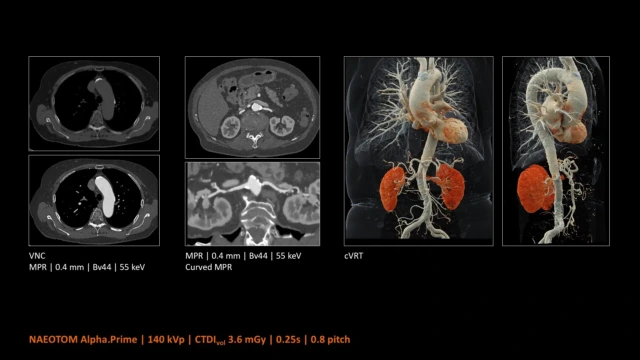

Il Pedorzoli di Peschiera del Garda è uno dei primi ospedali in Europa, e il primo in Italia, ad avere la TC Naetom Alpha.Prime, una “super tac” che grazie all’intelligenza artificiale riesce a individuare possibili patologie e traumi tra i 5 e i 10 secondi.

È un macchinario rivoluzionario che, grazie all’IA, permette ai pazienti di sottoporsi a un esame “total body” in pochi secondi. Inoltre, permette di verificare le condizioni mediche delle persone utilizzando un sesto delle radiazioni e solo metà del liquido di contrasto, grazie alla tecnologia a conteggio di fotoni (Photon Counting CT). Di fatto, in questo modo, anche chi soffre di insufficienza renale può essere visitato.

Ma questo non è l’unico vantaggio, infatti, sostenendo fino a 190 chili, permette anche alle persone che soffrono di obesità di sottoporsi all’esame e, durando così poco, è accettabile anche per i claustrofobici. Per di più, l’intelligenza artificiale è in grado di analizzare l’organismo di una persona anche se vestita o se ha il gesso, separando i vari strati e restituendo un’immagine ad alta definizione.

Grazie all’IA, è inoltre possibile diminuire i tempi per l’analisi dei dati, effettuati in automatico dalla macchina, e analizzare le condizioni del paziente da un esame all’altro, come quelli oncologici che sono costretti a farlo ogni 3 mesi. Il macchinario indica anche la posizione in cui va messa la persona per il test, permettendo un controllo più accurato possibile.